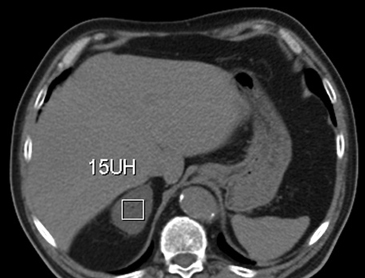

La presencia de lípidos intracelulares disminuye la densidad de la lesión debido a que estos son menos densos que el agua. El primer estudio en reportar la utilidad de la densitometría por TC en la diferenciación de una lesión suprarrenal benigna de una maligna fue el realizado por Lee et al6, utilizando la medición del coeficiente de atenuación o densidad de la lesión expresada en unidades Hounsfield (UH), en una TC no contrastada, demostrando que el coeficiente de atenuación promedio de los adenomas (2,2 UH) fue significativamente menor que la de las lesiones no adenomas (28,9 UH). Utilizando un punto de corte de 0 UH la sensibilidad de la TC no contrastada en la caracterización de un adenoma es cercana a un 47%, con una especificidad de aproximadamente 100% (Figura 9 a y b). Sin embargo, estudios posteriores7 han corroborado que al utilizar un punto de corte de 10 UH, la sensibilidad asciende a un 71%, y la especificidad se mantiene en prácticamente 98%, por lo que este umbral de densidad es el más utilizado en la actualidad. Es importante enfatizar que para una adecuada medición de la densidad, la región de interés (ROI) no debe incluir áreas de necrosis ni de hemorragia, y debe abarcar al menos la mitad o dos tercios de la lesión, para evitar el artefacto por ruido y el efecto de volumen parcial con el tejido adiposo adyacente (Figura 10).

Figura 10. Adenoma suprarrenal derecho. Lesión suprarrenal derecha, cuya densidad es consistente con un adenoma típico. En la imagen se demuestra una adecuada medición de la densidad lesional, con una región de interés (ROI) que abarca al menos dos tercios de ésta.

Los valores más utilizados son un 40% de lavado relativo de en fase tardía realizada a los 15 minutos y un lavado absoluto de 60%. De este modo cualquier lesión que muestre un lavado relativo mayor al 40% o absoluto mayor al 60% es consistente con un adenoma, con una sensibilidad y especificidad cercana al 100% (Figura 14 a, b y c). Dado la rapidez con que se obtiene un TAC de abdomen en la actualidad, algunos trabajos han recomendado utilizar cortes tardíos realizados a los 10 minutos, con el fin de optimizar el tiempo de examen, y utilizar un valor relativo de corte más conservador del 50%9.

C Figura 14. Tomografía computada de un adenoma suprarrenal izquierdo típico. Se ha colocado un circulo que representa la región de interés en la lesión de la glándula suprarrenal izquierda, obteniendo una medición promedio (Avg) expresada en unidades Hounsfield (UH). En fase precontraste (a) su densidad es de 0 UH, (flecha), en fase protovenosa (b) alcanza una densidad de 59 UH (cabeza de flecha), y en fase tardía (c) su lavado es de aproximadamente un 50%, llegando a una densidad de 30 UH.